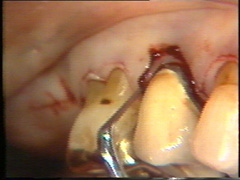

Se realiza una

segunda insición horizontal en el fondo de la bolsa para facilitar el levantamiento del tejido de

granulación

El levantamiento del tejido de

granulación se realiza en un tiempo y el procedimiento en sí es

exigente. Puede hacerse antes o después del levantamiento del colgajo.

El sangrado se controla bien y el tiempo de exposición del hueso

al medio bucal es reducido, cuando el tejido de granulación es

eliminado antes del levantamiento del colgajo.

Eliminación del

tejido de granulación |